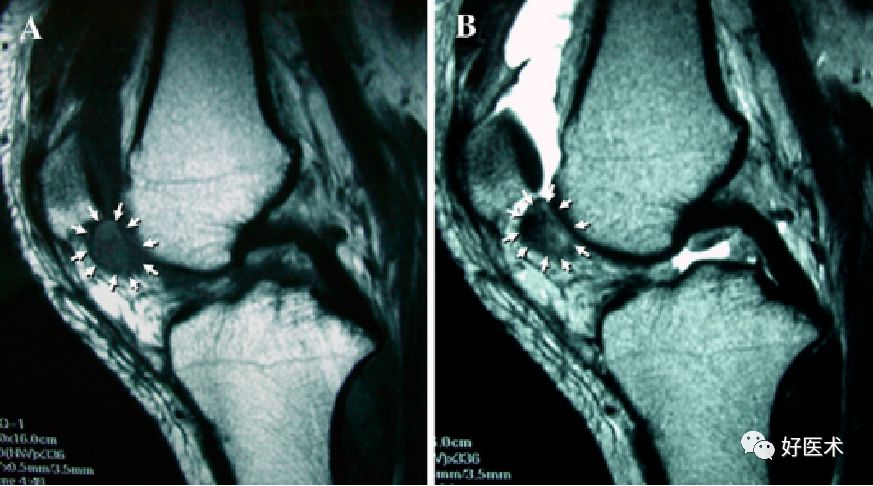

MRI表现

MRI对膝关节PVS具有定性诊断意义,它可以清楚显示病变的范围、关节软骨及骨质破坏的程度,其特征性表现为T1、T2加权像时低密度信号区。故MRI已成为X线片检查后首选的影像学检查方法。术前MRI检查不仅有助于明确关节内、外病变程度和范围,同时,术后MRI检查也是检查病变复发与否的最敏感手段。

髌下脂肪囊及关节腔滑膜呈绒毛、结节样隆起,并可见形态不规则T1、T2双低信号含铁血黄素沉着,关节积液

滑膜弥漫增厚,髌上囊、髌下脂肪囊及关节腔滑膜呈绒毛、结节样隆起,并可见形态不规则T1、T2双低信号含铁血黄素沉着,关节积液